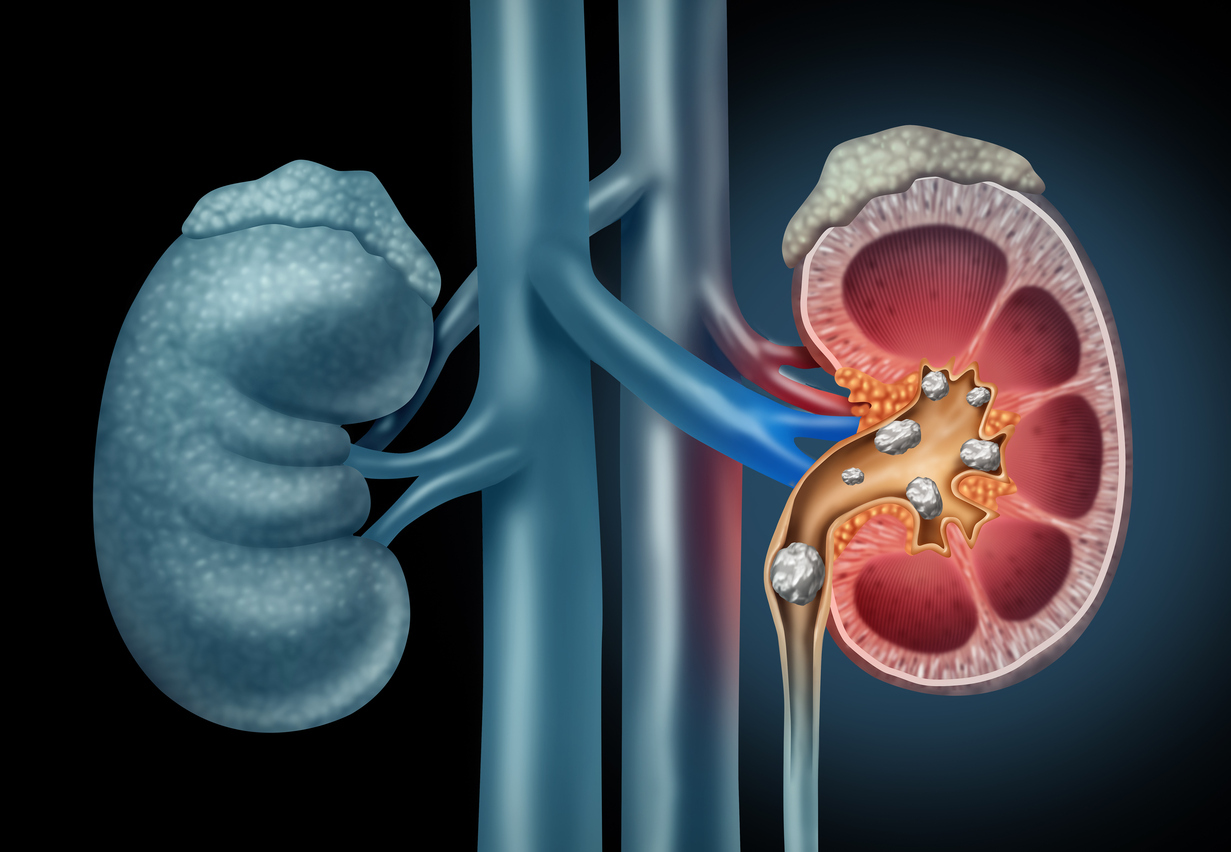

Η εμφάνιση λίθων στα νεφρά, αποτελεί μια νόσο του ουροποιητικού συστήματος, η οποία κάνει την εμφάνισή της όταν υπάρχει αυξημένη συγκέντρωση ορισμένων ουσιών στα ούρα, που οδηγούν στο σχηματισμό κρυστάλλων.

Οι κρύσταλλοι αυτοί, αποτελούνται στις περισσότερες περιπτώσεις από άλατα ασβεστίου ή ουρικού οξέος και μπορεί, ανάλογα με το μέγεθός τους, να περάσουν ελεύθερα από τον ουρητήρα και να αποβληθούν μέσω των ούρων, χωρίς να προκαλέσουν ιδιαίτερα συμπτώματα, ή να προκαλέσουν «φραγή» κάποιου σημείου του ουρητήρα, με αποτέλεσμα την εμφάνιση οξέος πόνου ή και άλλων συμπτωμάτων.

Η συχνότητα εμφάνισης της νόσου είναι σχετικά υψηλή και υπολογίζεται ότι περίπου 1 στους 10 ενήλικες θα εμφανίσει κάποια στιγμή στη ζωή του νεφρολιθίαση, με τον κίνδυνο να είναι υψηλότερος για τους άνδρες.

Επιπλέον, φαίνεται ότι άτομα που έχουν εμφανίσει μία φορά πέτρα/ες στους νεφρούς, έχουν αυξημένη πιθανότητα επανεμφάνισης, εάν δε ληφθούν απαραίτητα μέτρα πρόληψης.

Εξαιρώντας περιπτώσεις που η νεφρολιθίαση εμφανίζεται ως αποτέλεσμα κάποιας υποκείμενης παθολογικής κατάστασης ή νόσου, πρόκειται για μια κατάσταση που μπορεί να προληφθεί. Ειδικότερα, ορισμένες αλλαγές στη διατροφή και τον τρόπο ζωής μπορεί να συμβάλλουν σημαντικά στην πρόληψη της εμφάνισης ή επανεμφάνισης νεφρολιθίασης.

Παρακάτω θα βρείτε 6 απλούς τρόπους που μπορούν να σας προστατεύσουν από την εμφάνιση της νόσου:

Πίνετε επαρκείς ποσότητες υγρών, και κυρίως νερού, καθημερινά:

Η επαρκής πρόσληψη νερού και υγρών συμβάλλει στην αυξημένη παραγωγή ούρων, διευκολύνοντας την αποβολή των προϊόντων του μεταβολισμού, χωρίς να αυξάνεται η συγκέντρωσή τους, εμποδίζοντας έτσι το σχηματισμό κρυστάλλων. Μια απλή μέθοδος για να ελέγξετε τα επίπεδα υδάτωσης του οργανισμού είναι το χρώμα των ούρων. Πρακτικά, όσο πιο ανοιχτόχρωμα είναι τα ούρα σας, τόσο πιο ενυδατωμένοι είστε.

Μειώστε την πρόσληψη αλατιού-νατρίου:

Περιορίστε το προστιθέμενο αλάτι στο φαγητό και αποφύγετε τρόφιμα πλούσια σε αλάτι, όπως κονσερβοποιημένα τρόφιμα, παστά ψάρια, αλμυρά τυριά, αλλαντικά, λουκάνικα, λαχανικά σε μορφή τουρσί, έτοιμους χυμούς/ σάλτσες/ ζωμούς/ σούπες λαχανικών, αλατισμένα σνακ (κράκερ, πατατάκια κτλ.)/ ξηρούς καρπούς.

Αποφύγετε την υπερκατανάλωση πρωτεΐνης ζωικής προέλευσης:

Η συχνή κατανάλωση τροφίμων όπως κόκκινο κρέας, πουλερικά, ψάρια, αυγά, γάλα και γαλακτοκομικά προϊόντα σε μεγάλες ποσότητες μπορεί να αυξήσει τον κίνδυνο εμφάνισης νεφρολιθίασης, επομένως μην το «παρακάνετε», ειδικότερα εάν έχετε ήδη εμφανίσει πέτρα/ες στους νεφρούς. Από την άλλη, ερευνητικά δεδομένα δείχνουν ότι το ασβέστιο που περιέχεται στα τρόφιμα δε σχετίζεται με αυξημένο κίνδυνο εμφάνισης νεφρολιθίασης, συνεπώς δεν υπάρχει λόγος αποφυγής των γαλακτοκομικών προϊόντων.

Δώστε προσοχή στη λήψη συμπληρωμάτων διατροφής:

Έχει φανεί ότι η πρόσληψη υψηλών ποσοτήτων ορισμένων θρεπτικών συστατικών, όπως οι βιταμίνες C και E και το ασβέστιο, πιθανόν να σχετίζεται με αυξημένο κίνδυνο εμφάνισης της νόσου. Επομένως, εάν λαμβάνετε συμπληρώματα διατροφής, φροντίστε η δοσολογία των εν λόγω συστατικών να μην υπερβαίνει τη συνιστώμενη ημερήσια πρόσληψη.

Αποφύγετε την υπερκατανάλωση τροφίμων που είναι πλούσια σε οξαλικά οξέα:

Η αυξημένη πρόσληψη οξαλικών οξέων έχει φανεί ότι μπορεί να συμβάλλει στη δημιουργία πέτρας/ων στους νεφρούς, επομένως θα ήταν καλό να μη γίνεται υπερκατανάλωση τροφίμων που είναι πλούσια σε αυτά όπως το τσάι, η σοκολάτα, το σπανάκι, τα παντζάρια, οι μπάμιες, οι φράουλες, οι ξηροί καρποί και τα προϊόντα σόγιας.

Διατηρήστε ένα υγιές σωματικό βάρος:

Η παχυσαρκία έχει συσχετισθεί με αυξημένο κίνδυνο εμφάνισης νεφρολιθίασης. Συνεπώς, εάν έχετε υπερβάλλον σωματικό βάρος επιδιώξτε σταδιακή απώλεια.